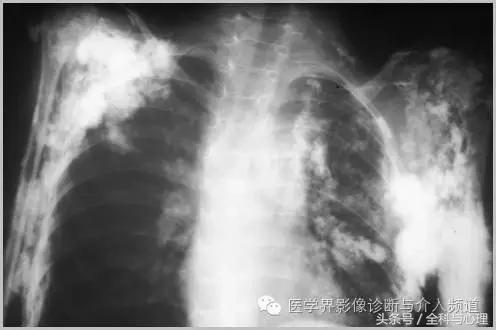

三、与胶原血管病相关的钙化

1、全身性钙质沉着症:皮肤、皮下或深部结缔组织钙化,与多种代谢紊乱及胶原血管病变有关,如皮肌炎,看起来像异位骨化,但没有真正的骨形成。开始为浅表的结节状或斑块状钙化,逐渐向更深的组织发展,表现为关节周围大片状钙化灶。

皮肌炎